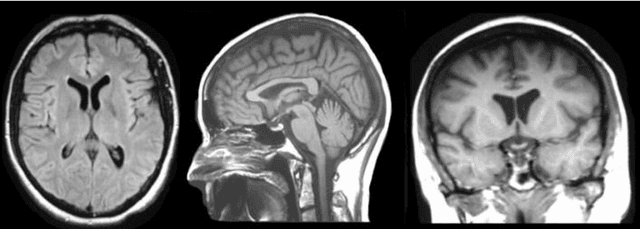

Abstract:Brain tumor segmentation intends to delineate tumor tissues from healthy brain tissues. The tumor tissues include necrosis, peritumoral edema, and active tumor. In contrast, healthy brain tissues include white matter, gray matter, and cerebrospinal fluid. The MRI based brain tumor segmentation research is gaining popularity as; 1. It does not irradiate ionized radiation like X-ray or computed tomography imaging. 2. It produces detailed pictures of internal body structures. The MRI scans are input to deep learning-based approaches which are useful for automatic brain tumor segmentation. The features from segments are fed to the classifier which predict the overall survival of the patient. The motive of this paper is to give an extensive overview of state-of-the-art jointly covering brain tumor segmentation and overall survival prediction.